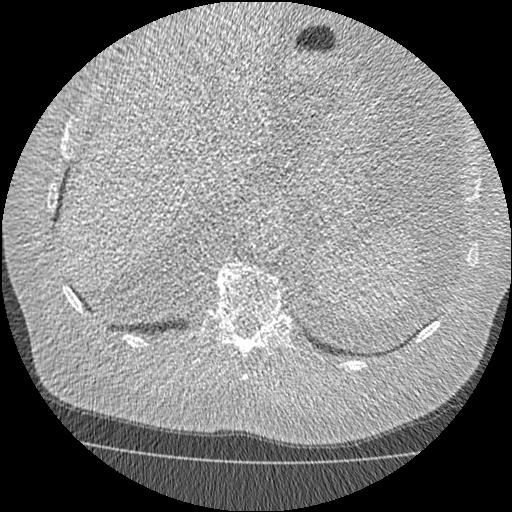

ХОБЛ и пневмофиброз на КТ

Пневмофиброз, ХОБЛ